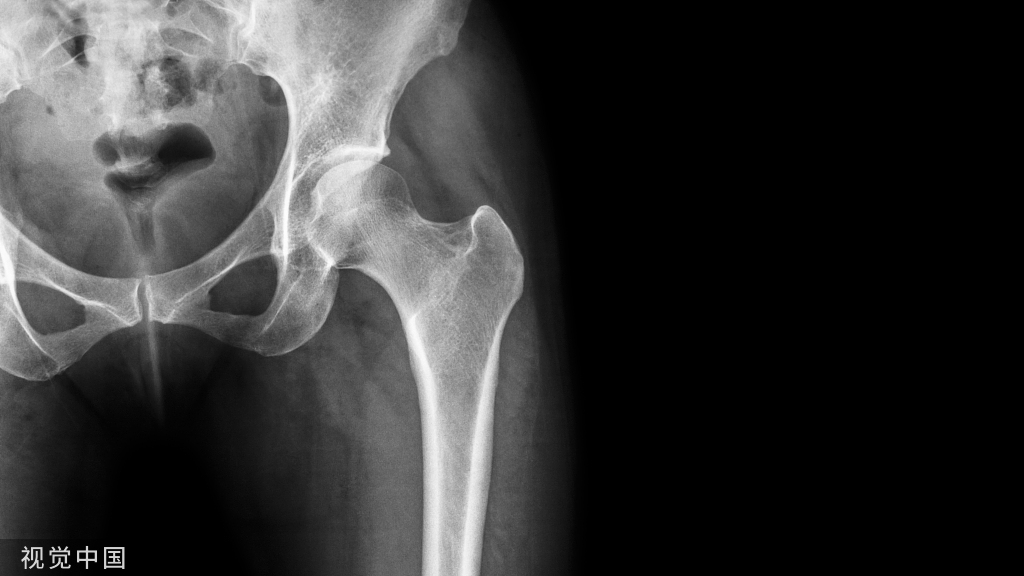

正位片透视钉道在坐骨切迹上方。